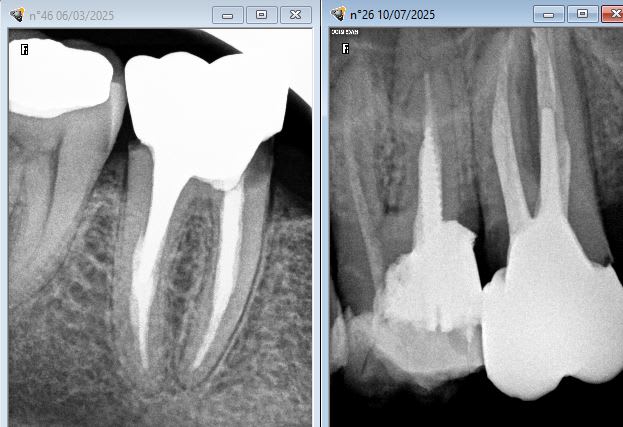

Tu ne trouves pas quand même qu'il y a plus de reprises carieuse sous rmipp composite? Même sous digue. Même (surtout) avec une remontée de marche. Je n'apprécie pas trop non plus les inlays cores.

Je fais beaucoup de dépose et je remarque que c’est dans la grande majorité des cas bien plus propre sous les inlay cores.

Je pense que c’est parce que c’est moins opérateur dépendant… Reconstruire un moignon de façon optimale quand les limites sont limites c’est bien compliqué. D’où les nombreuses infiltrations marginales quand tu ajoutes en plus la contraction de polymérisation.

Un inlay core poussé dans du ciment qui fuse c’est souvent plus sûr. Souvent couronne et inlay core sont nickels, mais l’ensemble est posé sur des endos inexistantes, c’est malheureux.

Quand c’est pas un inlay core tu peux être sûr que s’ajoutent infiltrations et caries.

T'as plein d'inlay cores avec reprises de carie aussi je peux t'en poster des caisses.

Des fois les ic c'est compliqué aussi. -)

C'est quoi le souci c'est la limite composite dent ? Si c'est au sec aucun souci sinon les indications des composites seraient très limitées. Bon là c'est un cas extrême mais tu fais tes RCPE avec des matrices au sec, ton endo et ensuite restauration avec screw post pas de raison que ça se carie. Les inlay cores scellés dans le sang en one shot avec la couronne ça marche moyen aussi. Les composites foulés dans la salive ça marche pas ca marche pas non plus avec une vis.